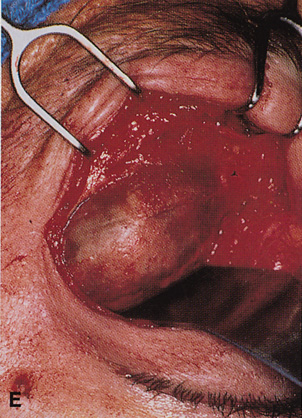

Fig. 6. Lateral orbitotomy through upper eyelid skin crease A. Photo demonstrating right globe ptosis present for more than 2 years. B. Axial CT scan showing a well outlined oval lesion in the lacrimal gland

fossa. C. Coronal CT showing lesion pushing globe inferiorly. D. Skin crease excision marked for lateral orbitotomy. E. Lateral orbital rim exposed. Bone cuts made above frontozygomatic suture

and at zygomatic arch. F. Lateral wall removed. Subperiosteal space exposed. Hard tumor could be

palpated in area of lacrimal gland. G. Benign mixed tumor of lacrimal gland removed. H. Bone sutured into place. I. Skin crease closed. |

zygomatic arch, which is even with the orbital floor (see Fig. 6E). Once the outer surface of the lateral rim has been exposed, the periorbita